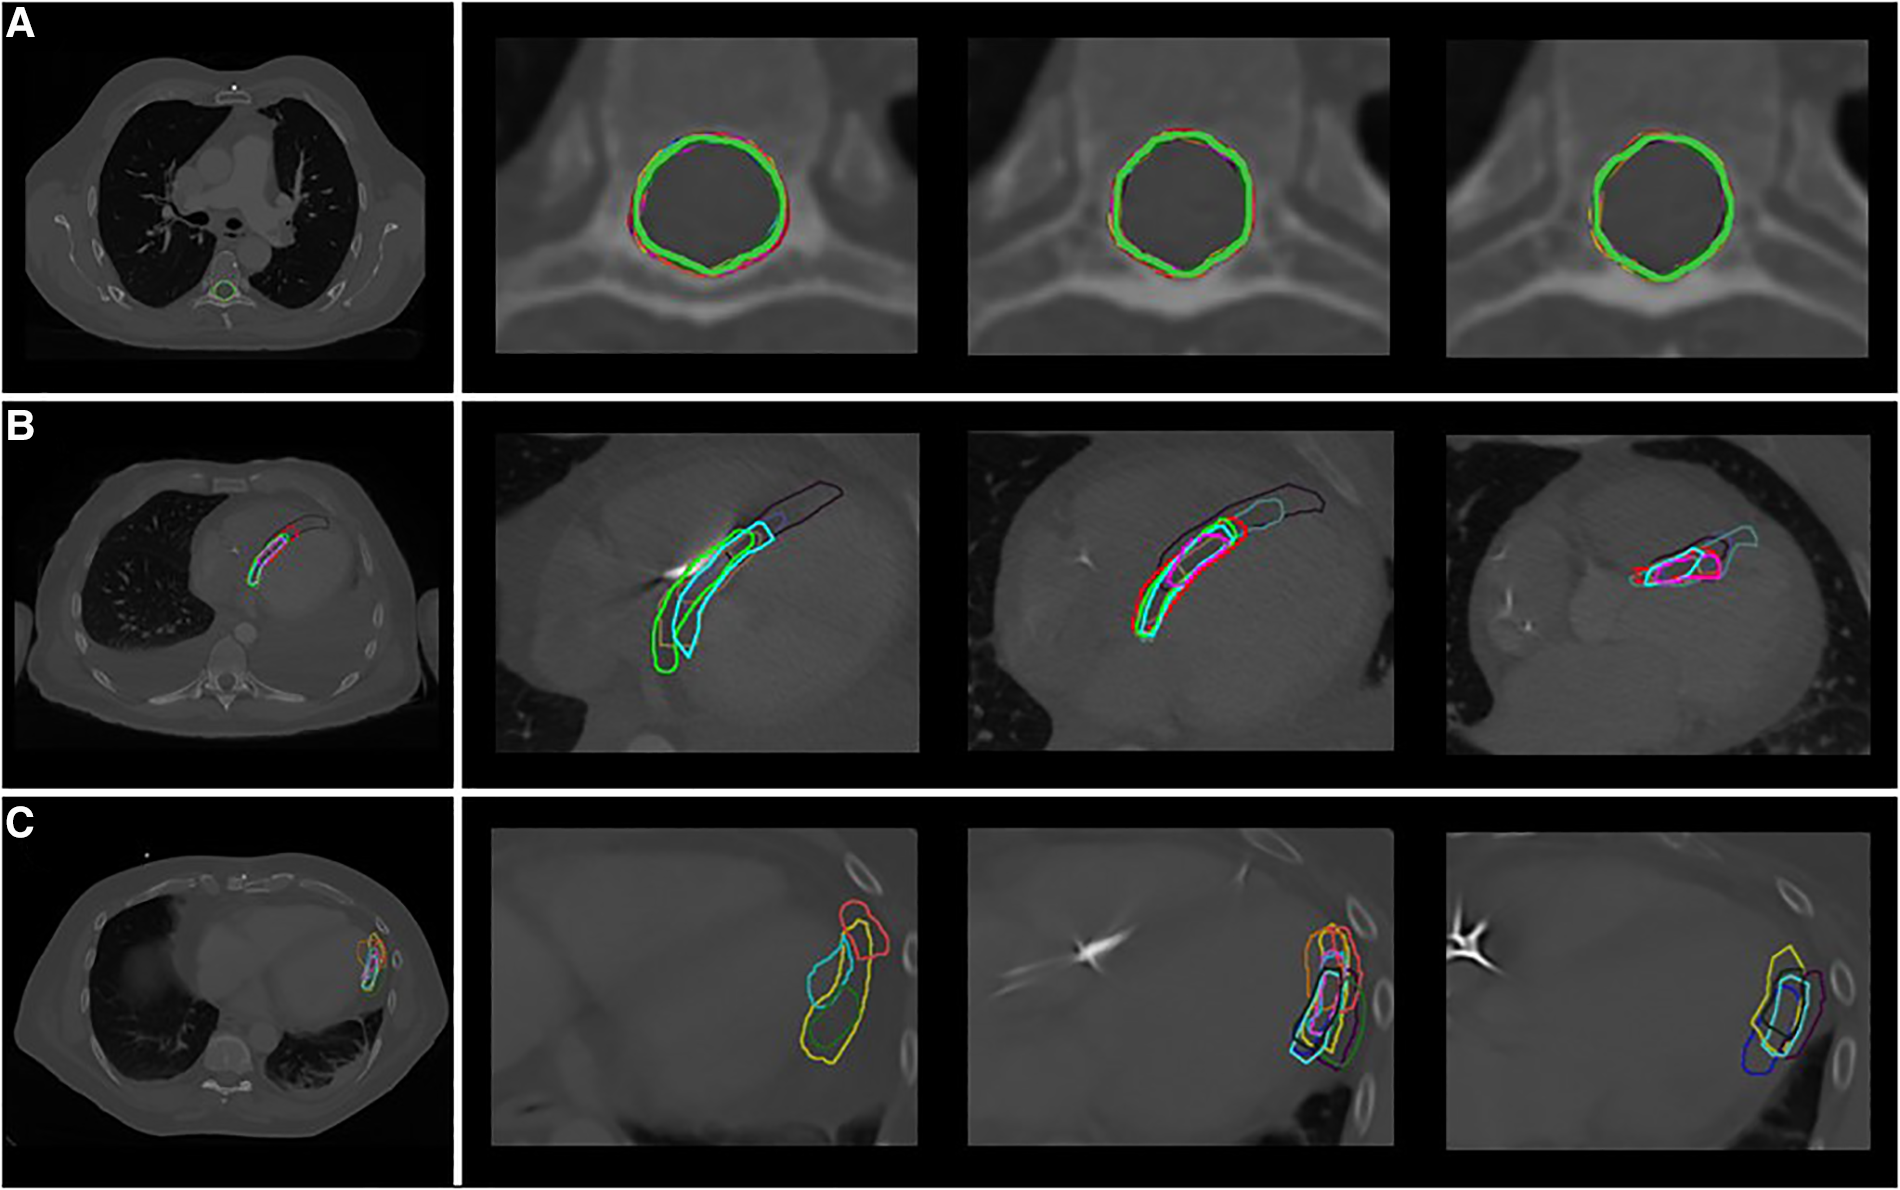

Figure 3

Delineations in representative cases by the different observers (A) phase 1: spinal canal, patient A (B) phase 2: VT-target, patient 2 (C) phase 3: segments, patient 3 (segment 16: apical-lateral). Each color indicates a different observer.

Low interobserver variation was found for the first phase of the study, the delineation of the spinal canal. This is indicated by low variation in the volumes (Table 2), low variation in distance to the median volume (RMS SD range 0.02–0.02 cm), and very high Dice coefficients (mean: 0.97 ± 0.01) (Table 2, Figures 3A, 4A).

Delineation of the VT-target based on case descriptions without advanced techniques resulted in high interobserver variability (Table 2, Figures 3B, 4B). The mean target volume ranged from 23–35 cm3 and widely differed per observer (range: 9.9–61.4 cm3, Table 2), as did the variation in distance to the median volume (RMS SD range: 0.5–1.02 cm, Table 2). The mean Dice coefficient for all three patients was 0.40 ± 0.15 with a range of 0.32–0.47 indicating low volume overlap.

Phase 3: segments

For phase 3, delineations of segments from the 17-segmented model showed equally high interobserver variation as phase 2 (Table 2, Figures 3C, 4C) as indicated by differences in delineated volumes between observers (Table 2), large variation in distance to the median volume (RMS SD range: 0.51–1.55 cm) and Dice coefficients below 0.5 (mean: 0.31 ± 0.21).